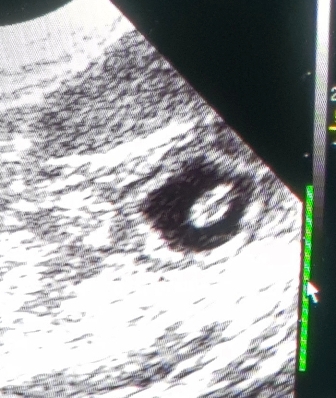

Aus Termingründen hatten wir den Ultraschall auf gestern Abend vorverlegt!

Noch sehr klein und schwer zu finden, haben wir sie trotzdem entdeckt :)

Juhuu, wir sind trächtig!!! Jippii

Hier die ersten Bilder unserer Kindlys:

Zählen war noch nicht möglich, sie zu erwischen war schon schwer ;) ;)

Ich denke wir konnten ca. 5 gut sehen..

Aber das heißt noch gar nichts!

Im Laufe der Woche, so um den 25-28 Tag, werde ich noch einmal schallen.

Erst danach, werde ich mich bei allen melden!

Wir freuen uns soo sehr!!!